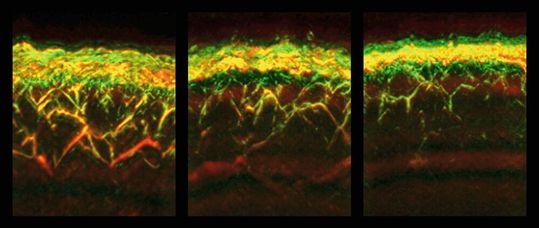

RSOM-Aufnahmen von der Haut eines gesunden Probanden (links), eines Patienten mit Diabetes (mitte) und eines Patienten mit Diabetes und Neuropathie (rechts).

Mit einer einzigen RSOM-Messung können gleichzeitig Daten aus verschiedenen Hautschichten gewonnen werden. So konnten die Forschenden erstmals feststellen, dass Diabetes die Gefäße in verschiedenen Hautschichten unterschiedlich beeinflusst: Während beispielsweise die Zahl der Gefäße und Verästlungen in der dermalen Ebene bei Diabetikern verringert war, waren sie dichter unter der Hautoberfläche, in der epidermalen Ebene, erhöht.